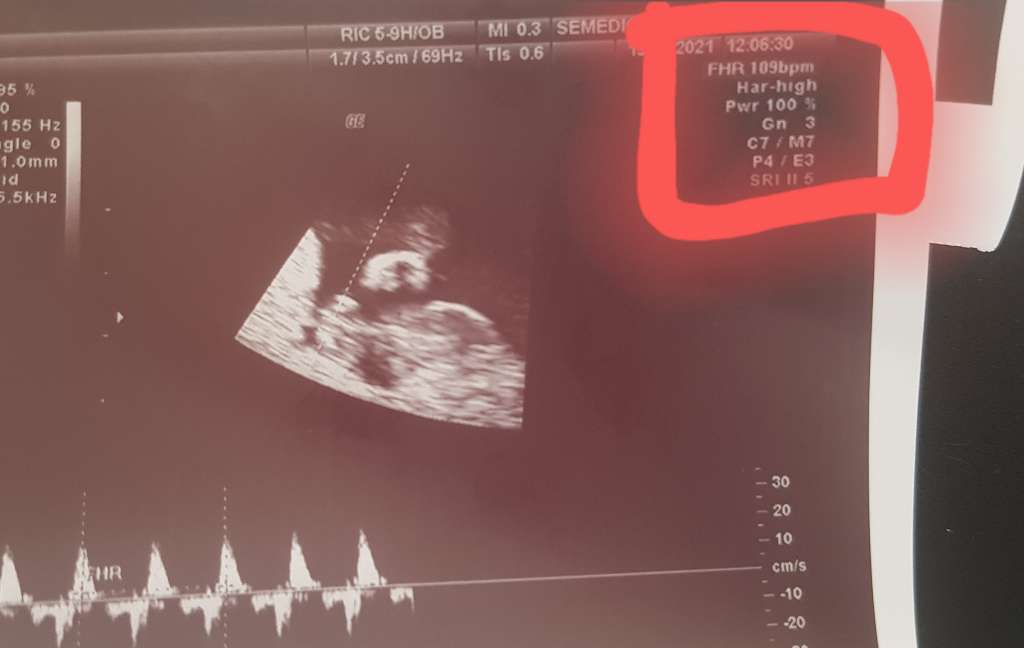

Tak patrzę sobie na zdjęcie z USG i tętno nie jest 105, tylko 109, wiem że to nieduża różnica, ale daje mi taką nadzieję.

Załączniki

• 1a5f7270-ad8c-4a0e-8bfc-b9bd7930711b.jpg

1a5f7270-ad8c-4a0e-8bfc-b9bd7930711b.jpg

28,3 KB · Wyświetleń: 112